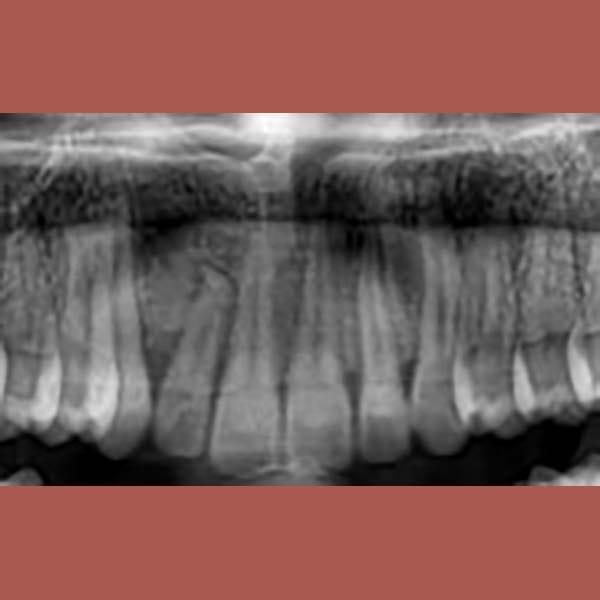

BEFORE